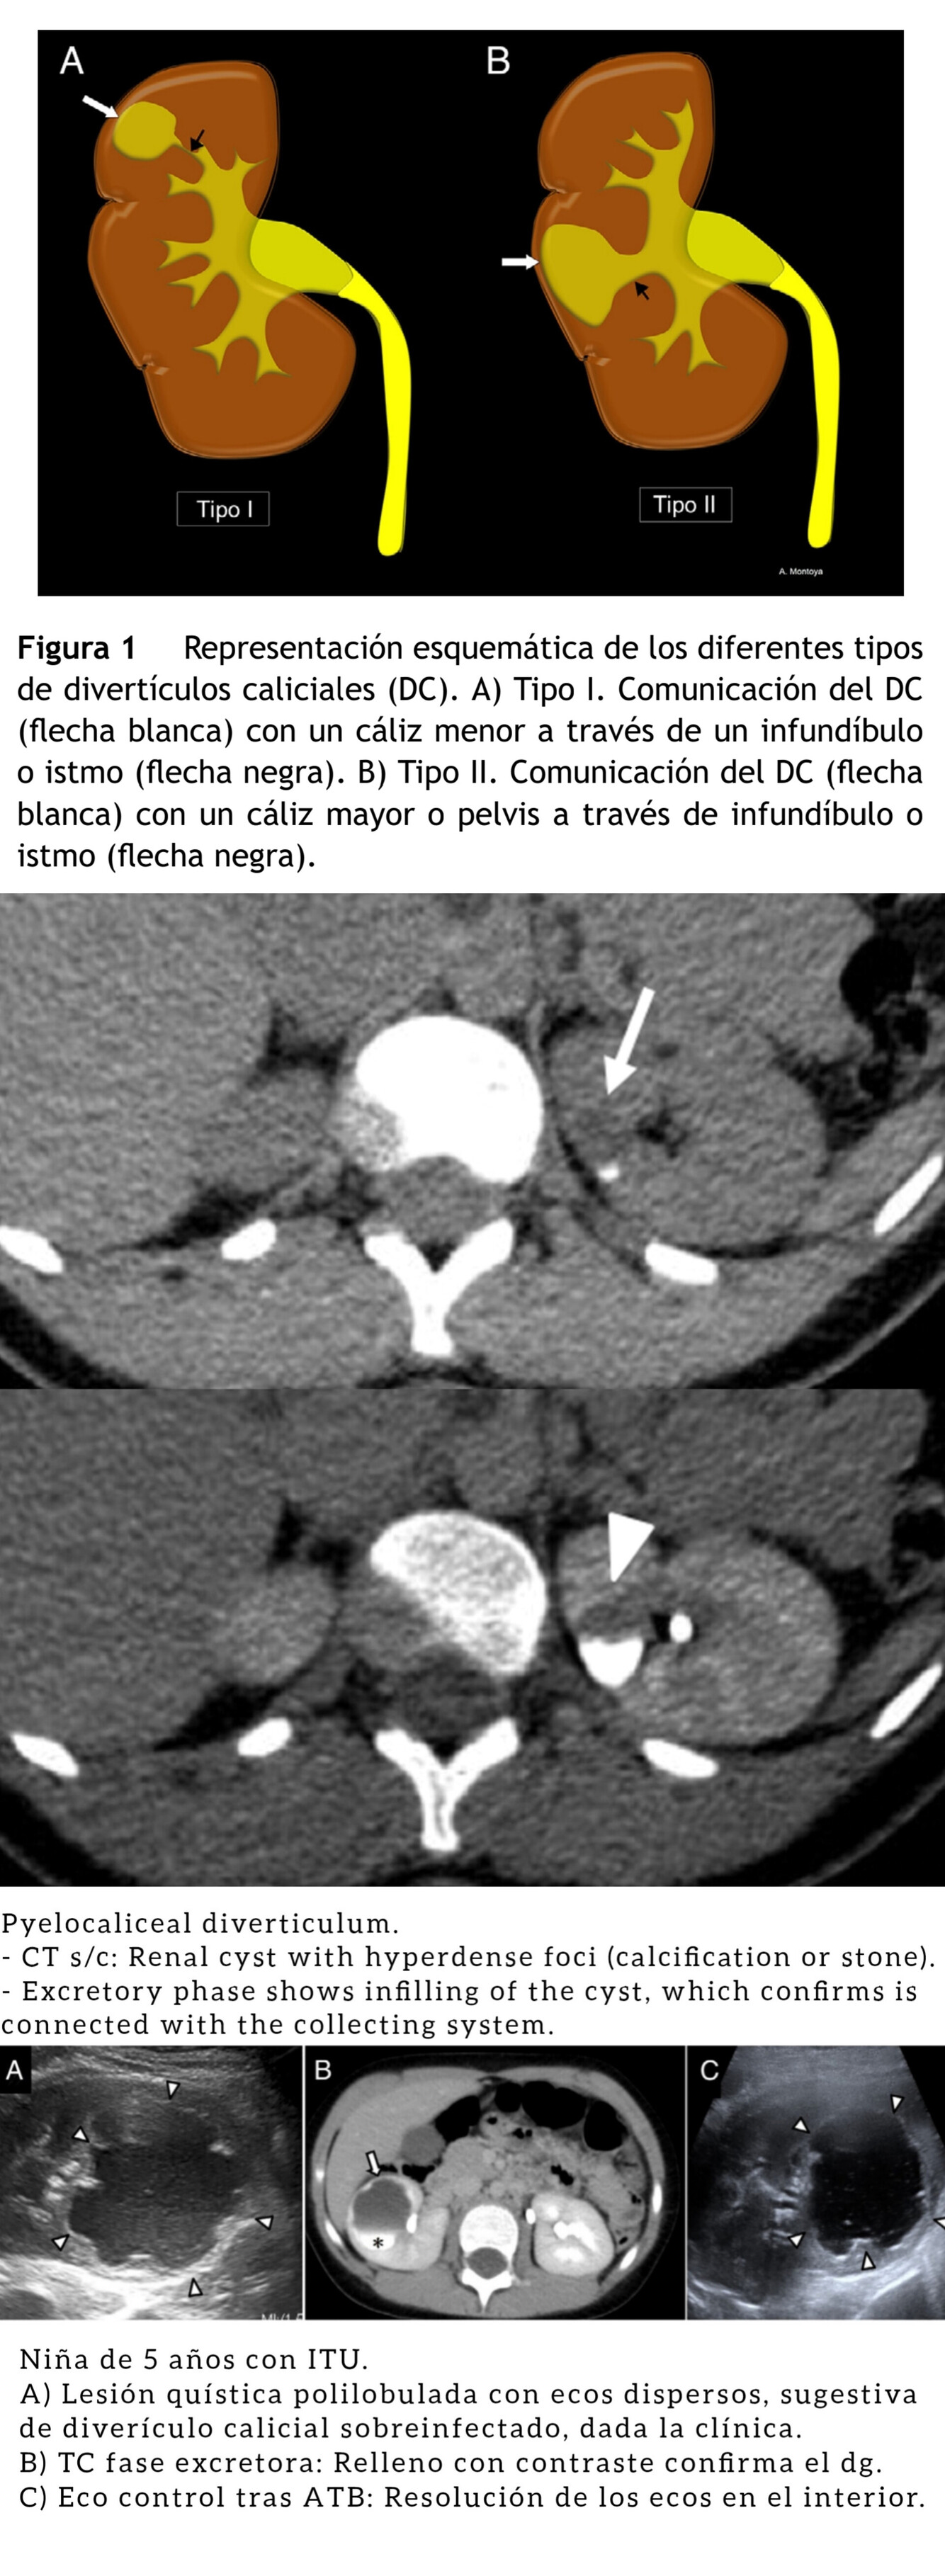

Divertículo Calicial.

Eventración quística intraparenquimatosa tapizada por epitelio celular transitorio con una estrecha conexión infundibular con los cálices o pelvis (término más exacto es divertículo pielocalicial).

Infradiagnosticado por confundirse con quistes; el dg confirma con

TC/RM) en fase excretora.